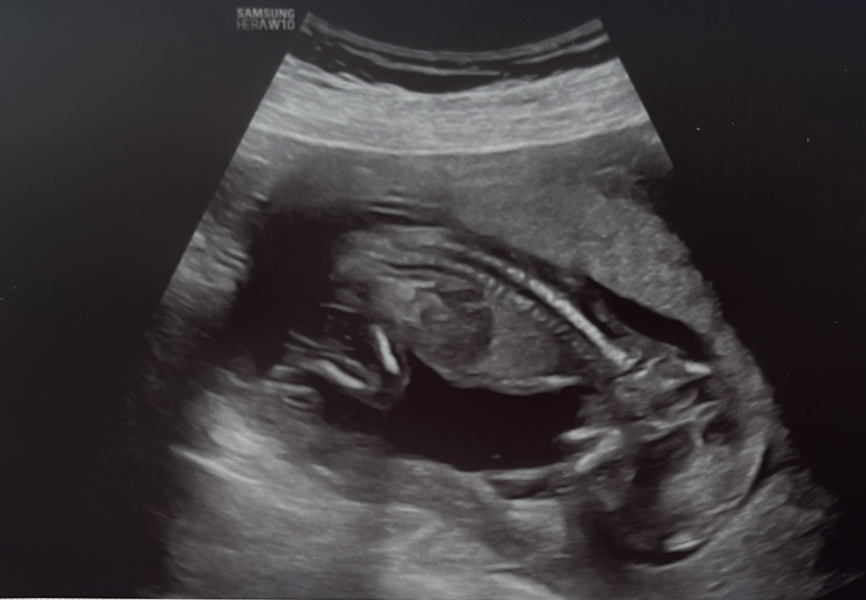

I got this nice picture from the scan showing the vertebrae :

ERA/Alice/Emma infertility thread graduates/pregnancies